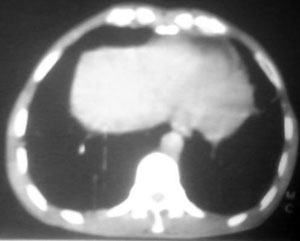

以下是引用逸风在2006-9-12 14:57:00的发言:[br]ct显示双肺上叶点片状及纤维索条状密度不均影,肺野外带近胸膜可见大小不等的含气空腔,壁略厚,境界清晰,未见液平面,中下肺野散在小片状及点状高密度影;纵隔内显示点状钙化,未见明显淋巴结肿大,构成胸廓诸骨未见明显异常.[br]诊断意见:1.双肺结核合并支气管播散;2.双肺上肺大泡.